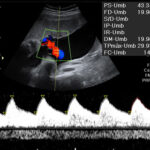

Ofrecemos servicios de ecografía obstétrica avanzada (genética, estructural, Doppler) y seguimiento experto de embarazos de alto riesgo, utilizando tecnología de punta para diagnósticos precisos

Servicios alineados con las directrices de la Fetal Medicine Foundation (FMF) y la International Society of Ultrasound in Obstetrics and Gynecology (ISUOG).